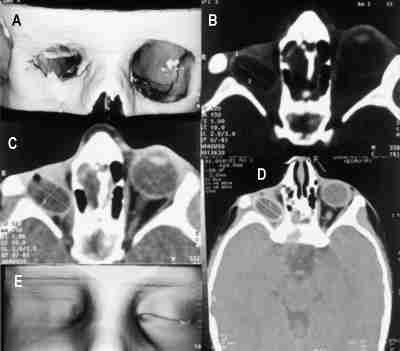

Los tumores grandes suelen tener márgenes peor definidos y al estar en contacto con los márgenes óseos orbitarios pueden adelgazar o erosionarlos e invadir estructuras vecinas como la glándula lacrimal o el nervio óptico (figura 5).

53-05.jpg (13291 bytes)

Figuras 5a y b. Rabdomiosarcoma orbitario izquierdo. Secuencia potenciada en T1 con gadolínio y saturación grasa (a) y potenciada en T2 (b). El tumor impronta el globo ocular y el cono muscular.

La RM muestra una masa de intensidad de señal similar al músculo o al cerebro en T1, hiperintensa en T2. La intensidad de señal puede variar si el tumor presenta áreas de hemorragia focal. El realce con contraste paramagnético es moderado-marcado.

La RM demuestra la extensión del tumor a senos paranasales (seno etmoidal) así como al compartimento intracraneal a través de la fisura orbitaria inferior.

El diagnóstico diferencial con lesiones inflamatorias (poco frecuentes en esta edad) así como con otros tumores orbitarios (leucemia, linfoma, hemangioma, linfangioma, granuloma eosinófilo) (figura 6), tumores de nervio periférico (el más frecuente el neurofibroma) (figura 7) puede ser más dificil ya que pueden presentar una intensidad de señal similar al RMS. En algunos casos es preciso diagnóstico histológico (15).

53-06.jpg (13316 bytes)

Figuras 6a y b. Granuloma eosinófilo que destruye el techo orbitario izquierdo e invade el parénquima cerebral. Secuencias de RM potenciadas en T1 con Gadolínio coronal (a) y sagital (b).

53-07.jpg (12729 bytes)

Figuras 7a, b, c y d. Neurinoma extraconal. Secuencia sagital T1 (a) y axial DP que muestra la lesión de localización extraconal. Las reconstrucciones coronales en ventana ósea (c) y parenquimatosa (d) de TC helicoidal permiten ver la lesión pue produce remodelación ósea, hallazgo típico de las lesiones de lento crecimiento.